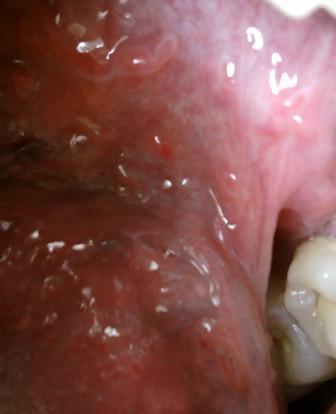

石家庄九州皮肤病医院 > 尖锐湿疣 > > > 初期尖锐湿疣可以手术治疗吗对于尖锐湿疣顽固性疾病,应该在早期坚持进行诊治,这是因为初期是治疗疾病的最佳时期,大家切记不要因为任何原因而耽误诊治,否则病情加重之后,对于人体健康带来的危害是很但大的。

初期尖锐湿疣可以手术治疗吗目前治疗尖锐湿疣的方法是比较多的,希望大家应该了解,根据病情来制定适合的治疗方法是很关键的,对症诊治,疾病才能迎刃而解,治疗方法不当只会错失治疗疾病的最佳时期。但是一般不建议采用手术治疗,这是因为手术治疗痛苦是比较大的,而且创伤面比较大,恢复起来是需要时间的,俄日护理不当,复发的几率是比较高的。